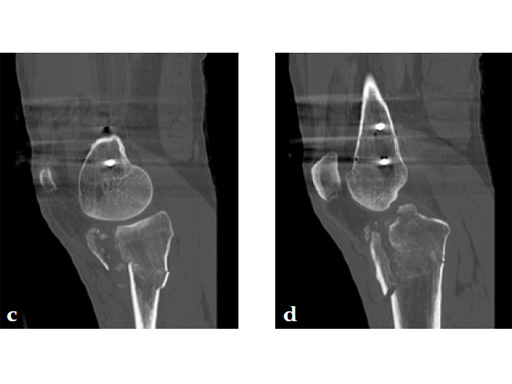

A 36-year-old man sustained a motorcycle injury: right femoral shaft fracture and right hyperextension bicondylar tibial plateau variant (Fig 1, Fig 2).

Staged management with initial rodding of femur and placement of spanning knee external fixator with closed manipulative reduction of tibial plateau (Fig 3).